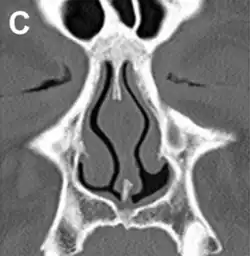

Diagnosis

No consensus criteria exist for the diagnosis of ENS and many ENTs will wait a year before diagnosing in hopes the patient accepts the new airflow; it is typically diagnosed by ruling out other conditions, with ENS remaining the likely diagnosis if the signs and symptoms are present.[3][7][13] A "cotton test" has been proposed, in which moist cotton is held where a turbinate should be or in various locations in the nasal passages, to see if it provides relief and an airflow pattern that allows for natural breathing; while this has not been validated nor is it widely accepted, it may be useful to identify which people may benefit from surgery.[3][7][13]